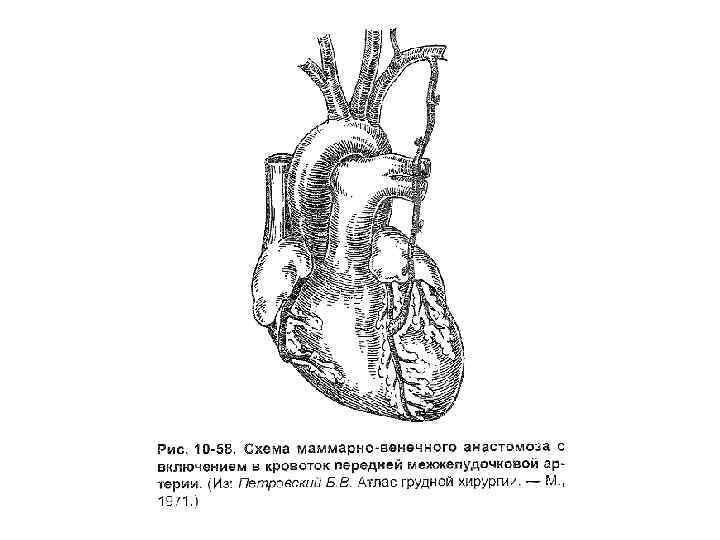

Имплантация внутренней грудной артерии в миокард (операция Вайнберга) • Создание анастомоза между внутренней грудной артерией и передней межжелудочковой ветвью левой венечной артерии.

Имплантация внутренней грудной артерии в миокард (операция Вайнберга) • Создание анастомоза между внутренней грудной артерией и передней межжелудочковой ветвью левой венечной артерии.

Операция Фиески • Перевязывание внутренних грудных артерий с двух сторон -> усиление кровотока по перикардодиафрагмальной артерии. • Операция дает удовлетворительный эффект, но не может остановить прогрессирующее течение коронарного атеросклероза. • При множественном поражении венечных артерий полная реваскуляризация миокарда с помощью внутренней грудной артерии не всегда возможна.

Операция Фиески • Перевязывание внутренних грудных артерий с двух сторон -> усиление кровотока по перикардодиафрагмальной артерии. • Операция дает удовлетворительный эффект, но не может остановить прогрессирующее течение коронарного атеросклероза. • При множественном поражении венечных артерий полная реваскуляризация миокарда с помощью внутренней грудной артерии не всегда возможна.